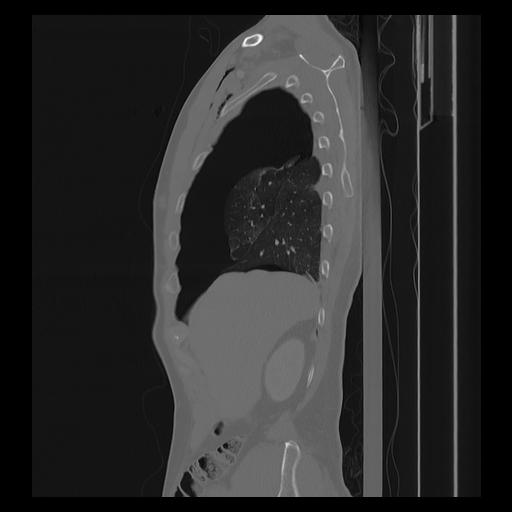

33 PULMON,CE,Sagittal,3.000,PULMON,Sagittal,